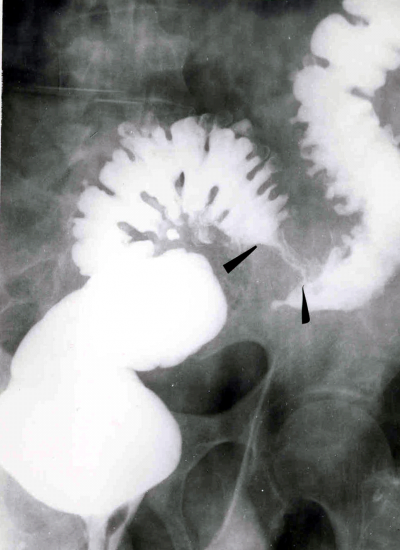

- חוקן בריום: בחולים בלא סיבוכים אפשר לראות סעיפים הבולטים מדופן הכרכשת. לאחר ההתרוקנות נשאר הבריום בסעיפים, והם בולטים בצילום הבטן (תצלום 11.6). בחולים הלוקים בדלקת, בחוקן בריום אפשר לראות עווית, בצקת של הדופן והדגמה של הסעיפים באזורים סמוכים. לפעמים קשה להבדיל מצב זה משאת של הכרכשת (תצלום 12.6). במחלה סעיפית אפשר לראות נגיעות של מקטע, עווית שלו וסעיפים במקומות אחרים.

בחוקן בריום אפשר לראות היצרות של המקטע הנגוע, בצקת ואיבוד הצורה השקית (Saccular) של המעי.